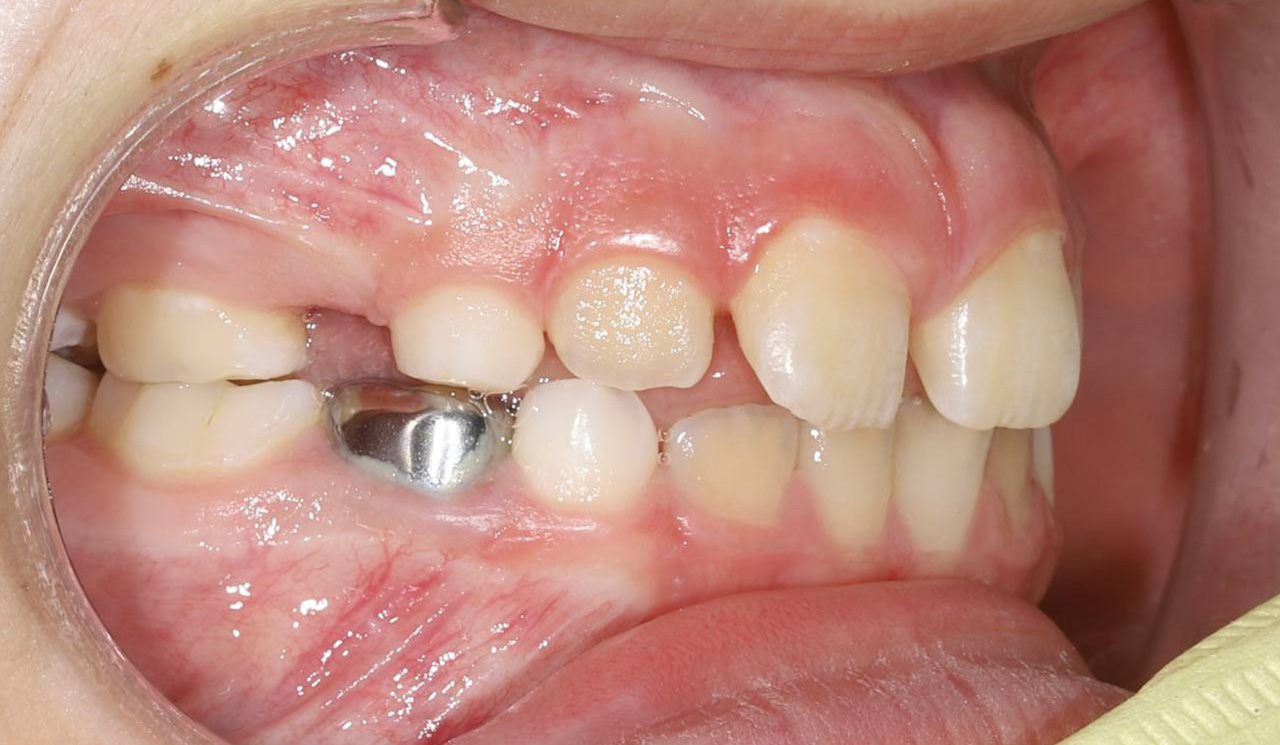

Подготовка к имплантации с помощью брекетов Experience